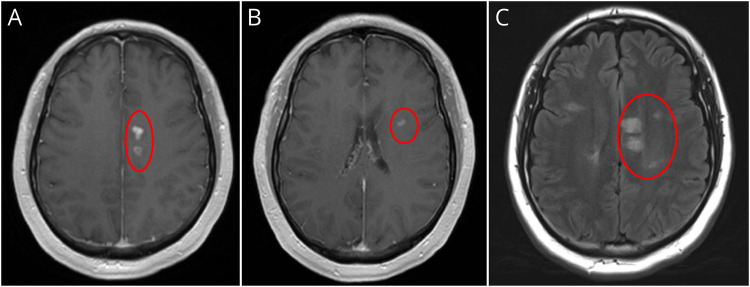

A 46-year-old man presented with progressive painful monocular vision loss and left leg paresthesias. Workup demonstrated multifocal demyelinating lesions and CSF-restricted oligoclonal bands. He was diagnosed with multiple sclerosis (MS), but follow-up testing was notable for positive myelin oligodendrocyte glycoprotein-immunoglobulin G (MOG-IgG). We discuss implications and clinical considerations for MOG-IgG positivity in MS.